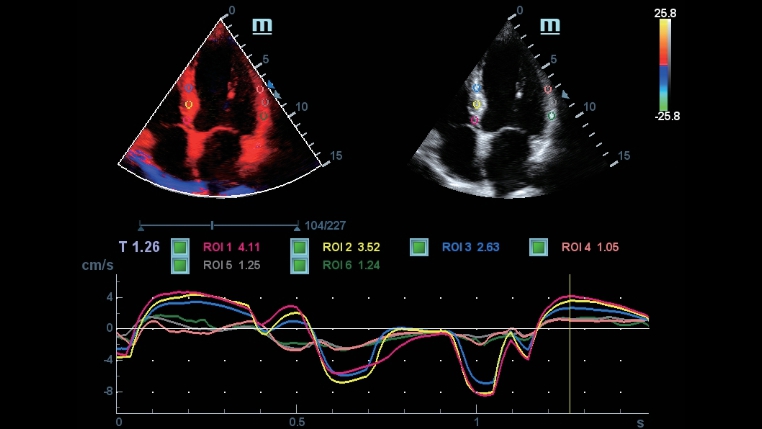

TÞm uygulama ara?lar?: Rahatl?kla do?ruluk garantisi iTouchTM

Full HD ?zellikli DC-40, diyagnostik do?rulu?u en Þst dÞzeye ??kartan bir dizi ara? sunar. Genel G?rÞntÞleme, Jinekoloji ve Kardiyolojiâyi kapsayan, Full HD ?zellikli DC-40, verimlilik i?in basitle?tirilmi? i? ak???yla genel klinik uygulamalar i?in size eksiksiz bir ??zÞm sunar.